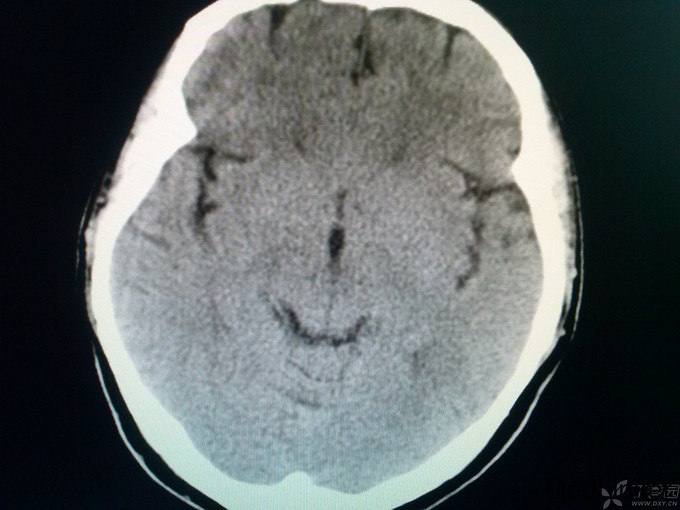

女患 40岁主诉:昏迷3个小时于4月26日入院 现病史:家属代诉患者于今晨7:30左右突然出现走路不稳,数分钟后昏迷,叫不醒,家属呼120来我医院,途中抽搐一次。 既往史:患者13岁时患风心病,04年行主动脉瓣及二尖瓣手术,为机械瓣,之后一直应用华法林1片口服,房颤史不明确,2年前有一过性昏迷症状,未在意。 上传27日CT:

查体:体温36.0℃,脉搏60次/分,呼吸20次/分,血压120/80mmHg。平车推入病房,查体不合作。皮肤巩膜无黄染,胸前见手术瘢痕,双肺呼吸音粗,未闻及罗音,心室率72次/分,律绝对不齐,无病理性杂音,腹部膨隆,膀胱区叩诊为浊音,肝脾肋下未触及。神经系统专科查体:嗜睡,双瞳孔同大同圆,双眼直径3.0mm,对光反射灵敏,双侧鼻唇沟对称,咽反射(+),四肢对疼痛刺激有反应,肌张力正常,肱二头肌、肱三头肌肌腱及膝反射、跟腱反射均亢进,病理征:Babinski征L(+),R(+),颈无抵抗,Kernig征(-)。头CT:未见异常;入院后给予甘露醇125毫升间隔12小时静点一次,呋塞米20毫克间隔12小时静点一次。给予华法林2.5mg日一次口服、奥扎格雷80mg日一次静滴、活血化瘀、营养神经治疗。如是您是首诊患者,有何不同治疗方案?双抗+华法林、稳定斑块合适吗?理由呢? 4月27日: 患者嗜睡,叫醒后,问话能正确回答,患者不能识别物体的形状,左右肢体能识别,查体:嗜睡,双瞳孔同大同圆,双眼直径3.0m,对光反射灵敏,双侧鼻唇沟对称,咽反射(+),四肢活动可,肌张力正常,肱二头肌、肱三头肌肌腱及膝反射、跟腱反射均亢进,病理征:Babinski征L(+),R(+),颈无抵抗,Kernig征(-)。今日复查头CT:后续提供。同时华法林改为3.75mg日一次口服。病灶进展?还是? 4月28日 患者嗜睡,叫醒后,患者左右肢体失认,失算,尿量尚可,心电监护示:血压:96/70mmHg,心率140次/分,律不齐,血氧饱和度99%,现查体:嗜睡,呼吸平稳,肢体疼痛刺激可动,双瞳孔直径3.0mm,对光反射灵敏,双巴氏征(+)。双下肢无浮肿。给予低分子肝素4100单位间隔12小时皮下注射,患者心室率快,给予西地兰0.2mg静推。病灶进展?还是? 5月1日 患者处于嗜睡状态,但嗜睡时间较前明显缩短,问话可答,但答非所问,看似条理清晰,实则“子无须有”,呈现“虚构现象”,如问“几个孩子”,说“1个”,“男孩还是女孩”,答曰“男孩”,实则没有;问“什么水果”,有时能答对,绝大多数回答错误;但患者说话声调低、音量小,复述正常,心电监护示:血压107/77mmHg,心率89次/分,SPO2:98%,查体:嗜睡状态,丘脑性失语,无面瘫,双瞳孔直径3.0mm,对光反射灵敏,双眼上视、下视受限,以下视明显,四肢肌力5级,肌张力正常,双巴氏征(+)。 4月29日CT: